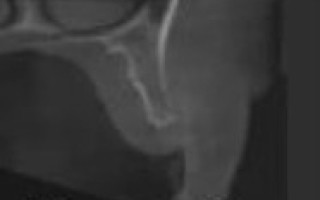

Le sinus-lift ou soulevé de sinus est une technique de chirurgie pré implantaire pour corriger les déficits osseux verticaux empêchant la fixation de l’implant dans l’os maxillaire postérieur (mâchoire du haut).

L’abord de l’os maxillaire se fait par une incision de la gencive.

Les tissus mous sont dégagés pour avoir accès à la paroi antérieure de l’os. Une fenêtre est découpée, pour avoir accès au sinus maxillaire sous-jacent : la muqueuse du sinus est décollée, pour y placer dessous le greffon préalablement préparé. Le greffon peut être de l’os d’origine humaine, animale ou synthétique. Le choix du matériau est réalisé en accord avec le patient.

Les plans sont refermés et la gencive suturée avec du fil résorbable.

Comme pour une greffe osseuse pré-implantaire, la consolidation optimale nécessite plusieurs mois. Un cone-beam permet de bien objectiver la réussite de cette consolidation.